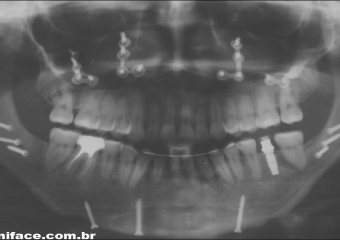

Raio x panorâmico final